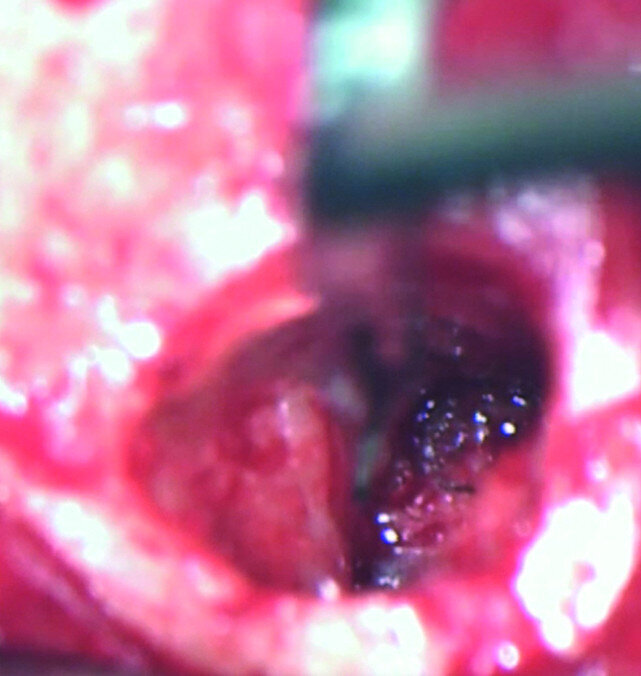

The treatment plan was to try to solve it with a conventional approach and if necessary to perform microsurgery to save the tooth. With the help of H-files, I managed to retrieve the cone from the palatal root, but the files inside the mesial root were impossible to bypass or even to reach with ultrasonic tips. I decided not to overdo it in order to avoid creating an additional problem, like perforating the canal, and decided to seal the canals (Fig. 10). A surgical approach was immediately taken for the mesial canals, cutting 3 mm of the mesial root using the Impact Air handpiece (SybronEndo), and this gave me a direct view of the Schneiderian membrane, where the third file was barely hanging (Figs. 11 & 12). I managed to delicate grab it and to remove it (Fig. 13). Figure 14 shows the postoperative situation, after performing retrograde preparation of the mesial canals.